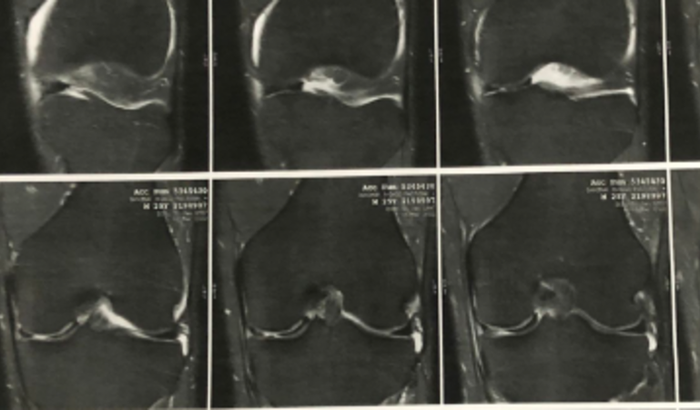

Eu sofri uma lesão no joelho (menisco/alça de balde) há 3 meses atrás, fui ao SUS que me colocou na fila de espera para cirurgia que levará muito tempo para se realizar. Fui também em outros 3 Médicos Ortopedistas particulares que também diagnosticaram cirurgia.